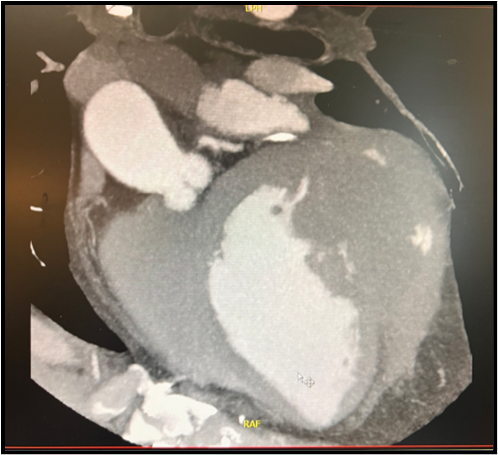

Angio CT of the chest dated 2/08/2024. – Extensive pseudoaneurysm of the anterolateral wall of the left ventricle, measuring approximately 55 x 65 x 90 mm (lumen). Heterogeneous thickness of the aneurysm wall – on the upper side thin (1-2 mm), on the posterolateral side thickened to 19-20 mm (adjacent thrombus?). Width of the aneurysm pedicle (defect in the wall of the left ventricle) – about 35x16 mm (Figure 3).

Figure 3: Chest computed angiotomography showing large left ventricular pseudoaneurysm